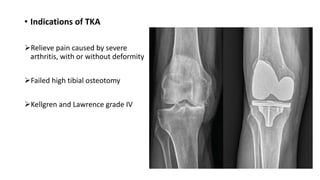

• Indications of TKA

Relieve pain caused by severe

arthritis, with or without deformity

Failed high tibial osteotomy

Kellgren and Lawrence grade IV